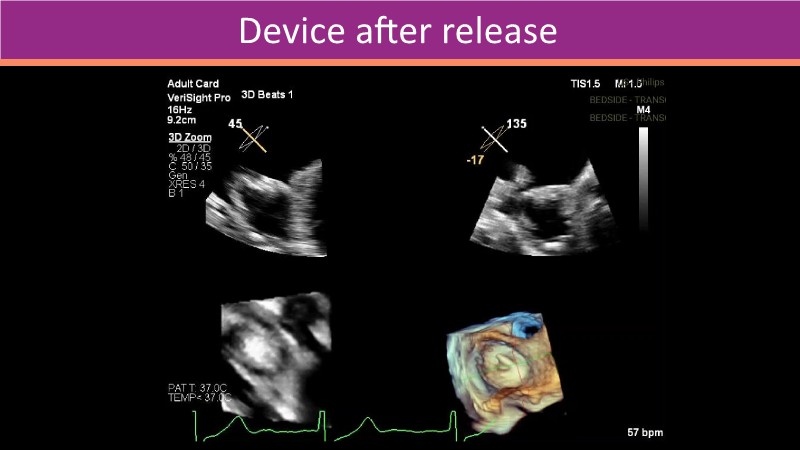

This PCR London Valves 2025 session explores how 3D TEE, 3D intracardiac echocardiography (ICE), and DeviceGuide technology sharpen procedural accuracy, strengthen operator confidence, and streamline decision-making in real time.

The session also includes detailed case analyses—such as Mitral TEER and LAA closure—and dual perspectives from both proceduralists and imagers.